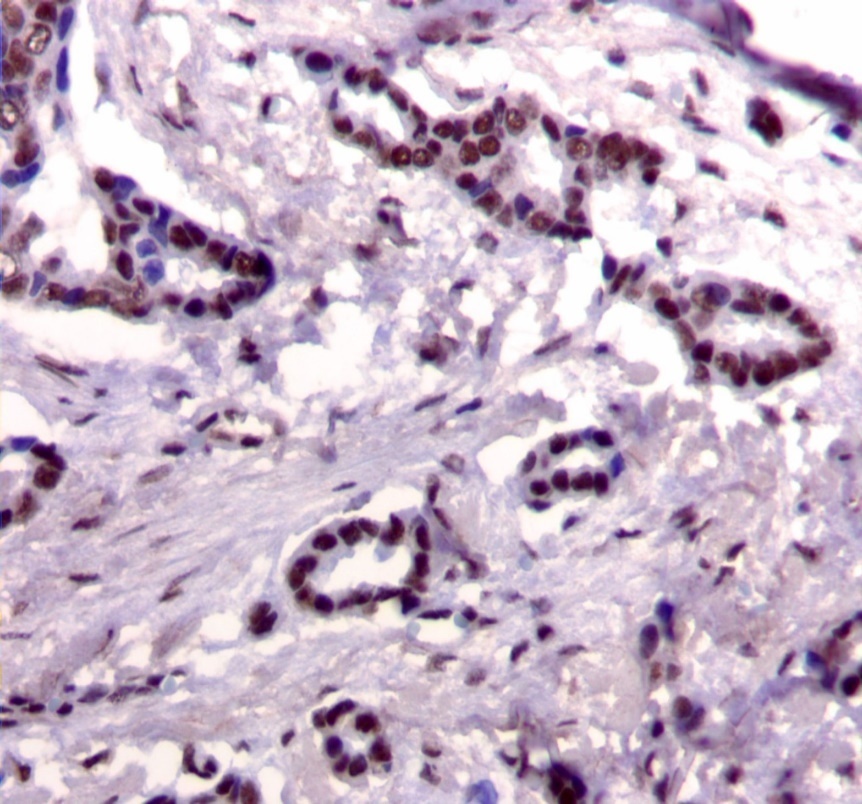

Figure 1.Nuclear staining pattern for IRS-1. (IRS-1 immunohistochemical stain, 200x magnification)

Nuclear staining pattern for IRS-1. (IRS-1 immunohistochemical stain, 200x magnification)

We used the following histologic criteria for IRS-1 and IRS-2 staining patterns which are outlined in a previous study.13 For IRS-1, a nuclear pattern was defined as diffuse nuclear staining (Figure 1). IRS-2 staining patterns were defined using the following criteria: Diffuse cytoplasmic staining was defined as evenly distributed cytoplasmic reactivity (Figure 2); punctate cytoplasmic staining was defined as clearly demarcated puncta of staining within the cytoplasm (Figure 3); and membrane staining was defined as focal or diffuse membranous staining (Figure 4). Sections of normal pancreas and normal breast tissue were used for positive and negative controls. The pathologists assessing staining patterns were blinded to the tumor recurrence score and all other data at the time of assessment.